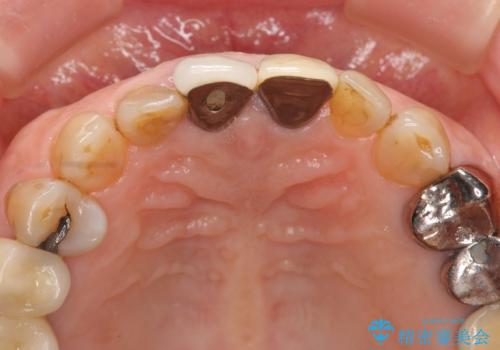

- 孫娘の結婚式に合わせて前歯を綺麗にして写真映りをよくしたいと来院されました。

結婚式に合わせて根管治療からのやりかえを短期集中治療で計4回で終える計画を立てます。

セラミック治療は外から見えるのはクラウンの色味・形態、歯肉の状態のみですが、X線撮影において現れるクラウンと歯牙の適合や、ファイバーコアの精度・根管充填の密度に、より長い予後を達成するための要素が含まれると考えます。